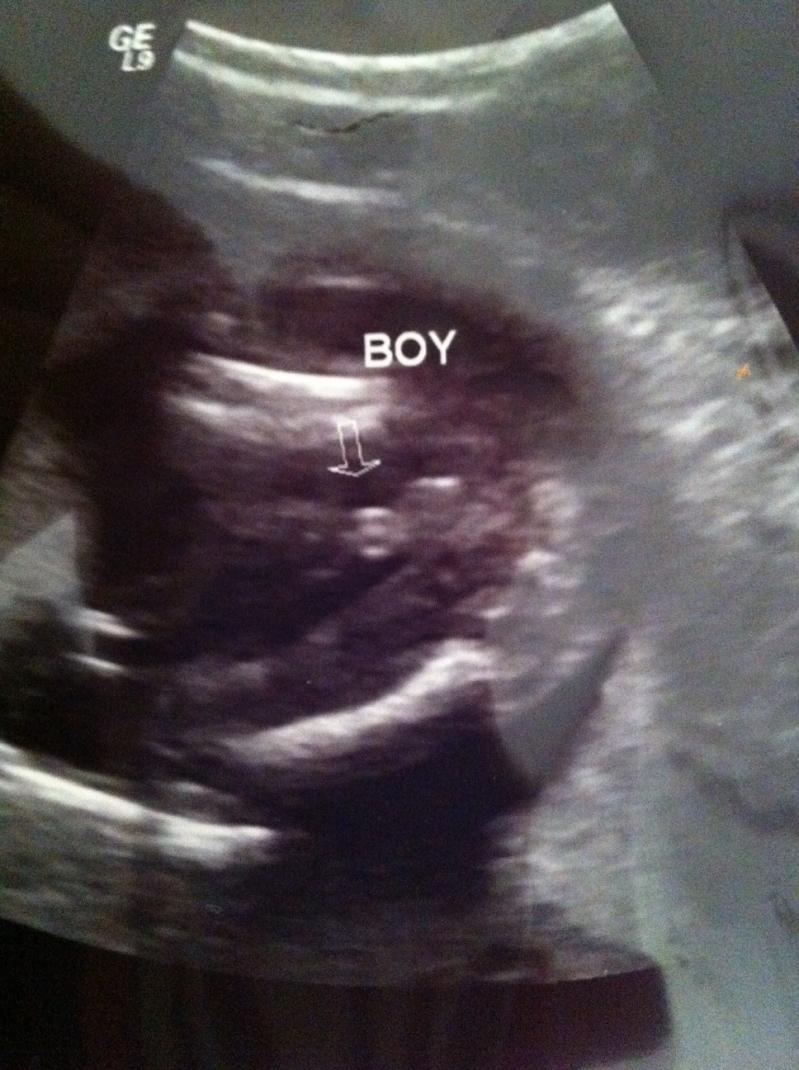

I'm 17w1d. Someone mentioned on other board about seeing 3 white lines but it just protrudes so much can't imagine that it's not a penis. Attachment 623

That's a:DS:! And I read somewhere that the penis can have 3 lines too .

Ok I see he suppose to be a girl? Sorry But look like a boy to me for sure.

Flava, she wanted a girl, in fact this is supposed to be a HT girl. I am not sure, the girlie parts are kinda like that, three lines....and they can be swollen. CT, I am SO sorry you are going through this....I have read your other thread and hope your mom was wrong. Will be praying this is just a swollen little va-jj.

Ok unless that's a cord and the other lines just under it (what suppose to be a scrotum) are the girl parts?

I really hope you can get a better pic then this because it's not so clear....look like boy but not that super clear boy pic like some others have.

Looks like a boy, sorry. Both penis and scrotum are present in this pic.

I think you need a clearer pic. It's just too blurry to be 100% sure. It looks nothing like my u/s pics of my boys. The penis was so obvious in their shots. I'll be praying that it's your girl in there! xoxo Blessings to you~~~

I think it could be cord. I am no expert, but on my 20 week scan that sonographer pointed out that the cord has 3 lines, they are the 3 blood vessels inside. It looks long like a cord. I hope for your sake that it is.

All boy!!

It is a boy